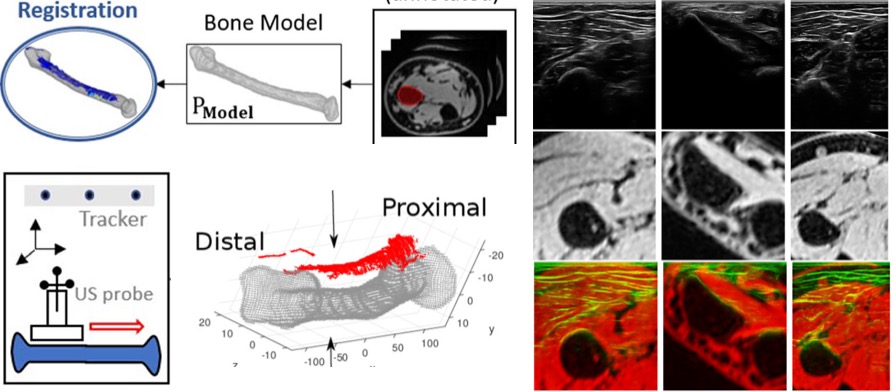

[2018] Matija Ciganovic, Firat Ozdemir, Fabien Pean, Philipp Fuernstahl, Christine Tanner, and Orcun Goksel:

"Registration of 3D Freehand Ultrasound to a Bone Model for Orthopaedic Procedures of the Forearm",

Int J Computer Assisted Radiology and Surgery 13(6):827-836, Jun 2018.

[2018] Matija Ciganovic, Firat Ozdemir, Fabien Pean, Philipp Fuernstahl, Christine Tanner, and Orcun Goksel:

"Registration of 3D Freehand Ultrasound to a Bone Model for Orthopaedic Procedures of the Forearm",

Int J Computer Assisted Radiology and Surgery 13(6):827-836, Jun 2018.

[2021] Lin Zhang, Tiziano Portenier, and Orcun Goksel:

"Learning Ultrasound Rendering from Cross-Sectional Model Slices for Simulated Training",

International Journal of Computer Assisted Radiology and Surgery 16:721-730, Apr 2021.

[2021] Lin Zhang, Tiziano Portenier, and Orcun Goksel:

"Learning Ultrasound Rendering from Cross-Sectional Model Slices for Simulated Training",

International Journal of Computer Assisted Radiology and Surgery 16:721-730, Apr 2021.